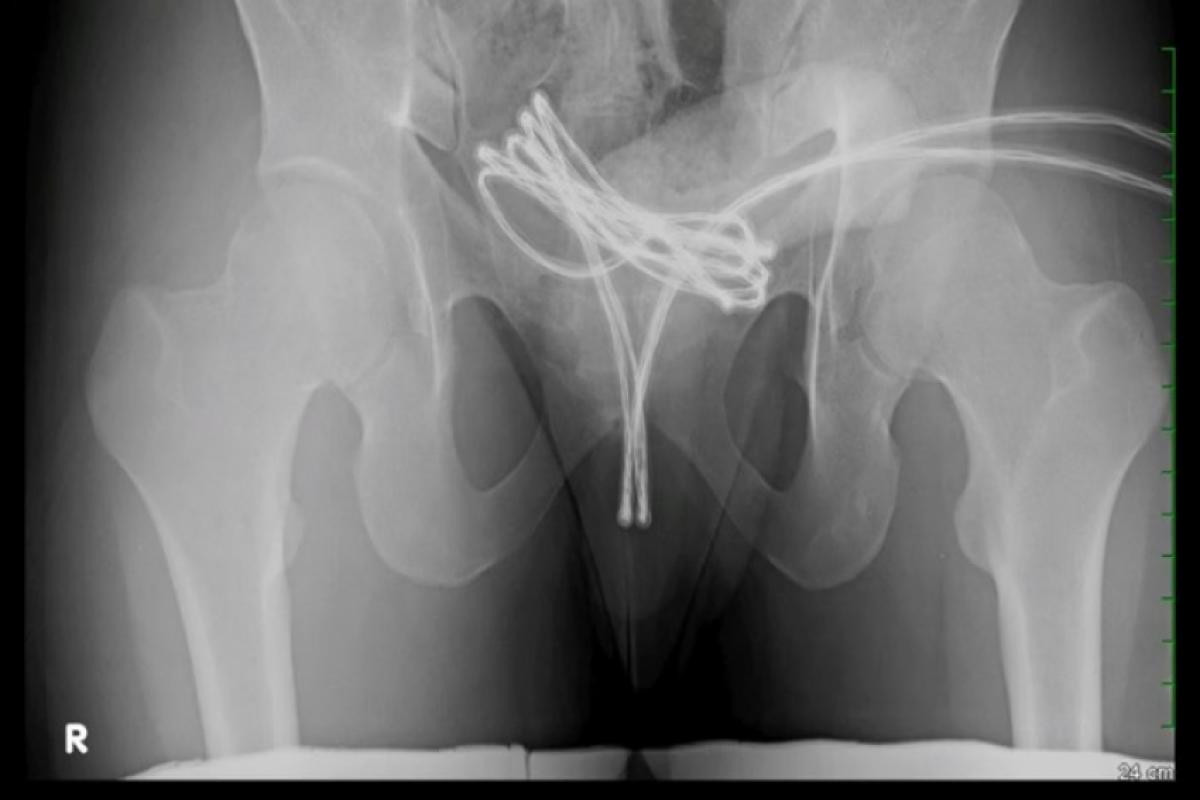

Os exames realizados mostraram que o cabo USB havia alcançado a bexiga do paciente, o que impediu a remoção por métodos menos invasivos. A equipe médica optou por um procedimento cirúrgico com anestesia geral, durante o qual foi introduzida uma câmera na uretra junto ao objeto, permitindo a retirada com segurança.

Após a intervenção, foram constatadas apenas lesões leves. O jovem recebeu antibióticos e analgésicos, além de um cateter urinário, utilizado por uma semana. Novos exames realizados posteriormente indicaram que não houve danos permanentes e que o paciente se recuperava de forma estável.